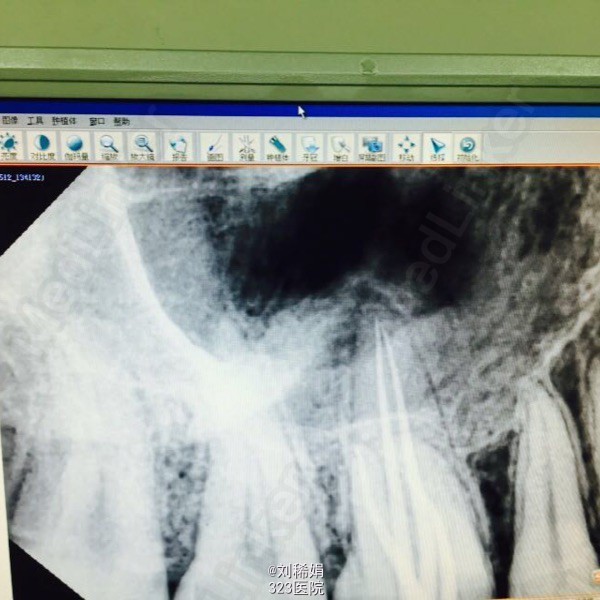

检查见右上第一磨牙邻(牙合)面补料脱落,大量继发龋。探痛明显,冷测疼痛。x线片显示龋损极近髓腔。

右上第一磨牙牙髓炎。遂做根管治疗处理,根管探查见腭侧双根管口,根管常规清理预备。

腭侧单根双管本人确实挺少见。所以拿出来跟大家分享一下。